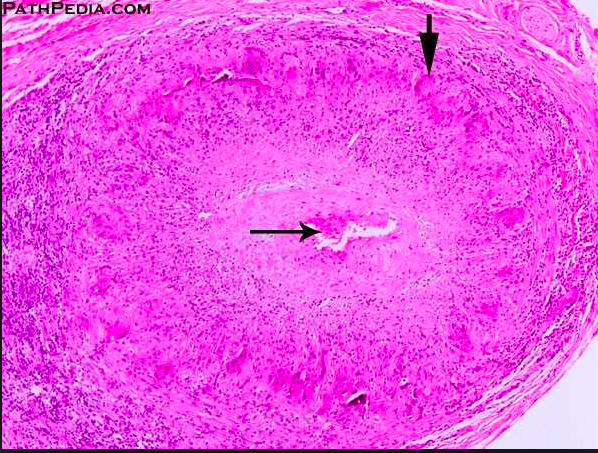

What is this?

Lesions of PN may vary in stages. Early lesions consist of transmural inflammation with fibrinoid necrosis that eventually heal with fibrosis, producing a ‘string of pearl’s appearance’ on imaging